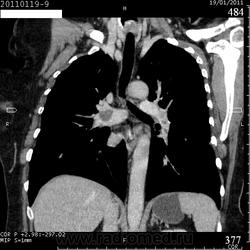

Коллега Mitkamfer спрашивал: "Может из наших коллег еще кто свои наблюдения покажет". Представляю случай ТЭЛА у женщины 57 лет с тромбозом подвздошной вены и распространением тромба в нижнюю полую вену.

Клиники особой не было, исследование делали с целью, а нет ли у нее еще и ТЭЛА. При КТ-ангиографии признаки пристеночных тромбов в правой и левой легочной артериях и единичных мелких пристеночных тромбов в мелких ветвях нижнедолевых артерий с обеих сторон, организовавшихся (лентовидных) тромбов в левой легочной артерии. При этом диаметры легочного ствола, правой и левой ЛА не расширены. Как видите, они такие разные, эти ТЭЛА

Изменения в легких при этом весьма скромные: в правом легком особых изменений нет, в левом - признаки организовавшегося инфаркта легкого - радиальные фиброзные тяжи в базально-латеральном сегменте нижней доли левого легкого.

Уважаемый, Андрей Юрьевич! В ходе диспута я неправильно Вас понял, думая, что Вы против наличия ТЭЛА. Анализируя представленные КТ-изображения (все они одного исследования), при ТЭЛА, изменения в легких - это признаки инфаркта легкого, в данном случае легкого линейно-тяжистого характера, хотя чаще он треугольной формы.

Рисунок 32. Дополнительные КТ-ангиографические признаки ТЭЛА у больной 58 лет.